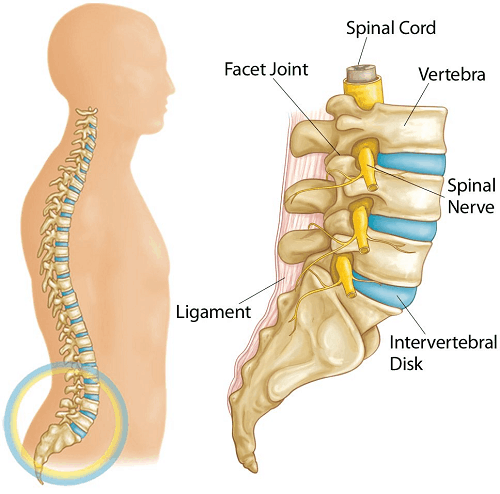

When we talk about a spinal disc, what we are actually talking about is a structure in your spine. The spine is made up of many bony segments called vertebrae and the structure in-between these segments are called your intervertebral discs (i.e. spinal disc).

It has a solid and strong exterior ligament component which provides stability and support, whilst there is a soft centre called the nucleus, which gives shock absorption of your body weight and for the various activities that you perform in a day. You could liken the disc to be a solid but gooey “lava-cake” sandwiched between crispy waffles.